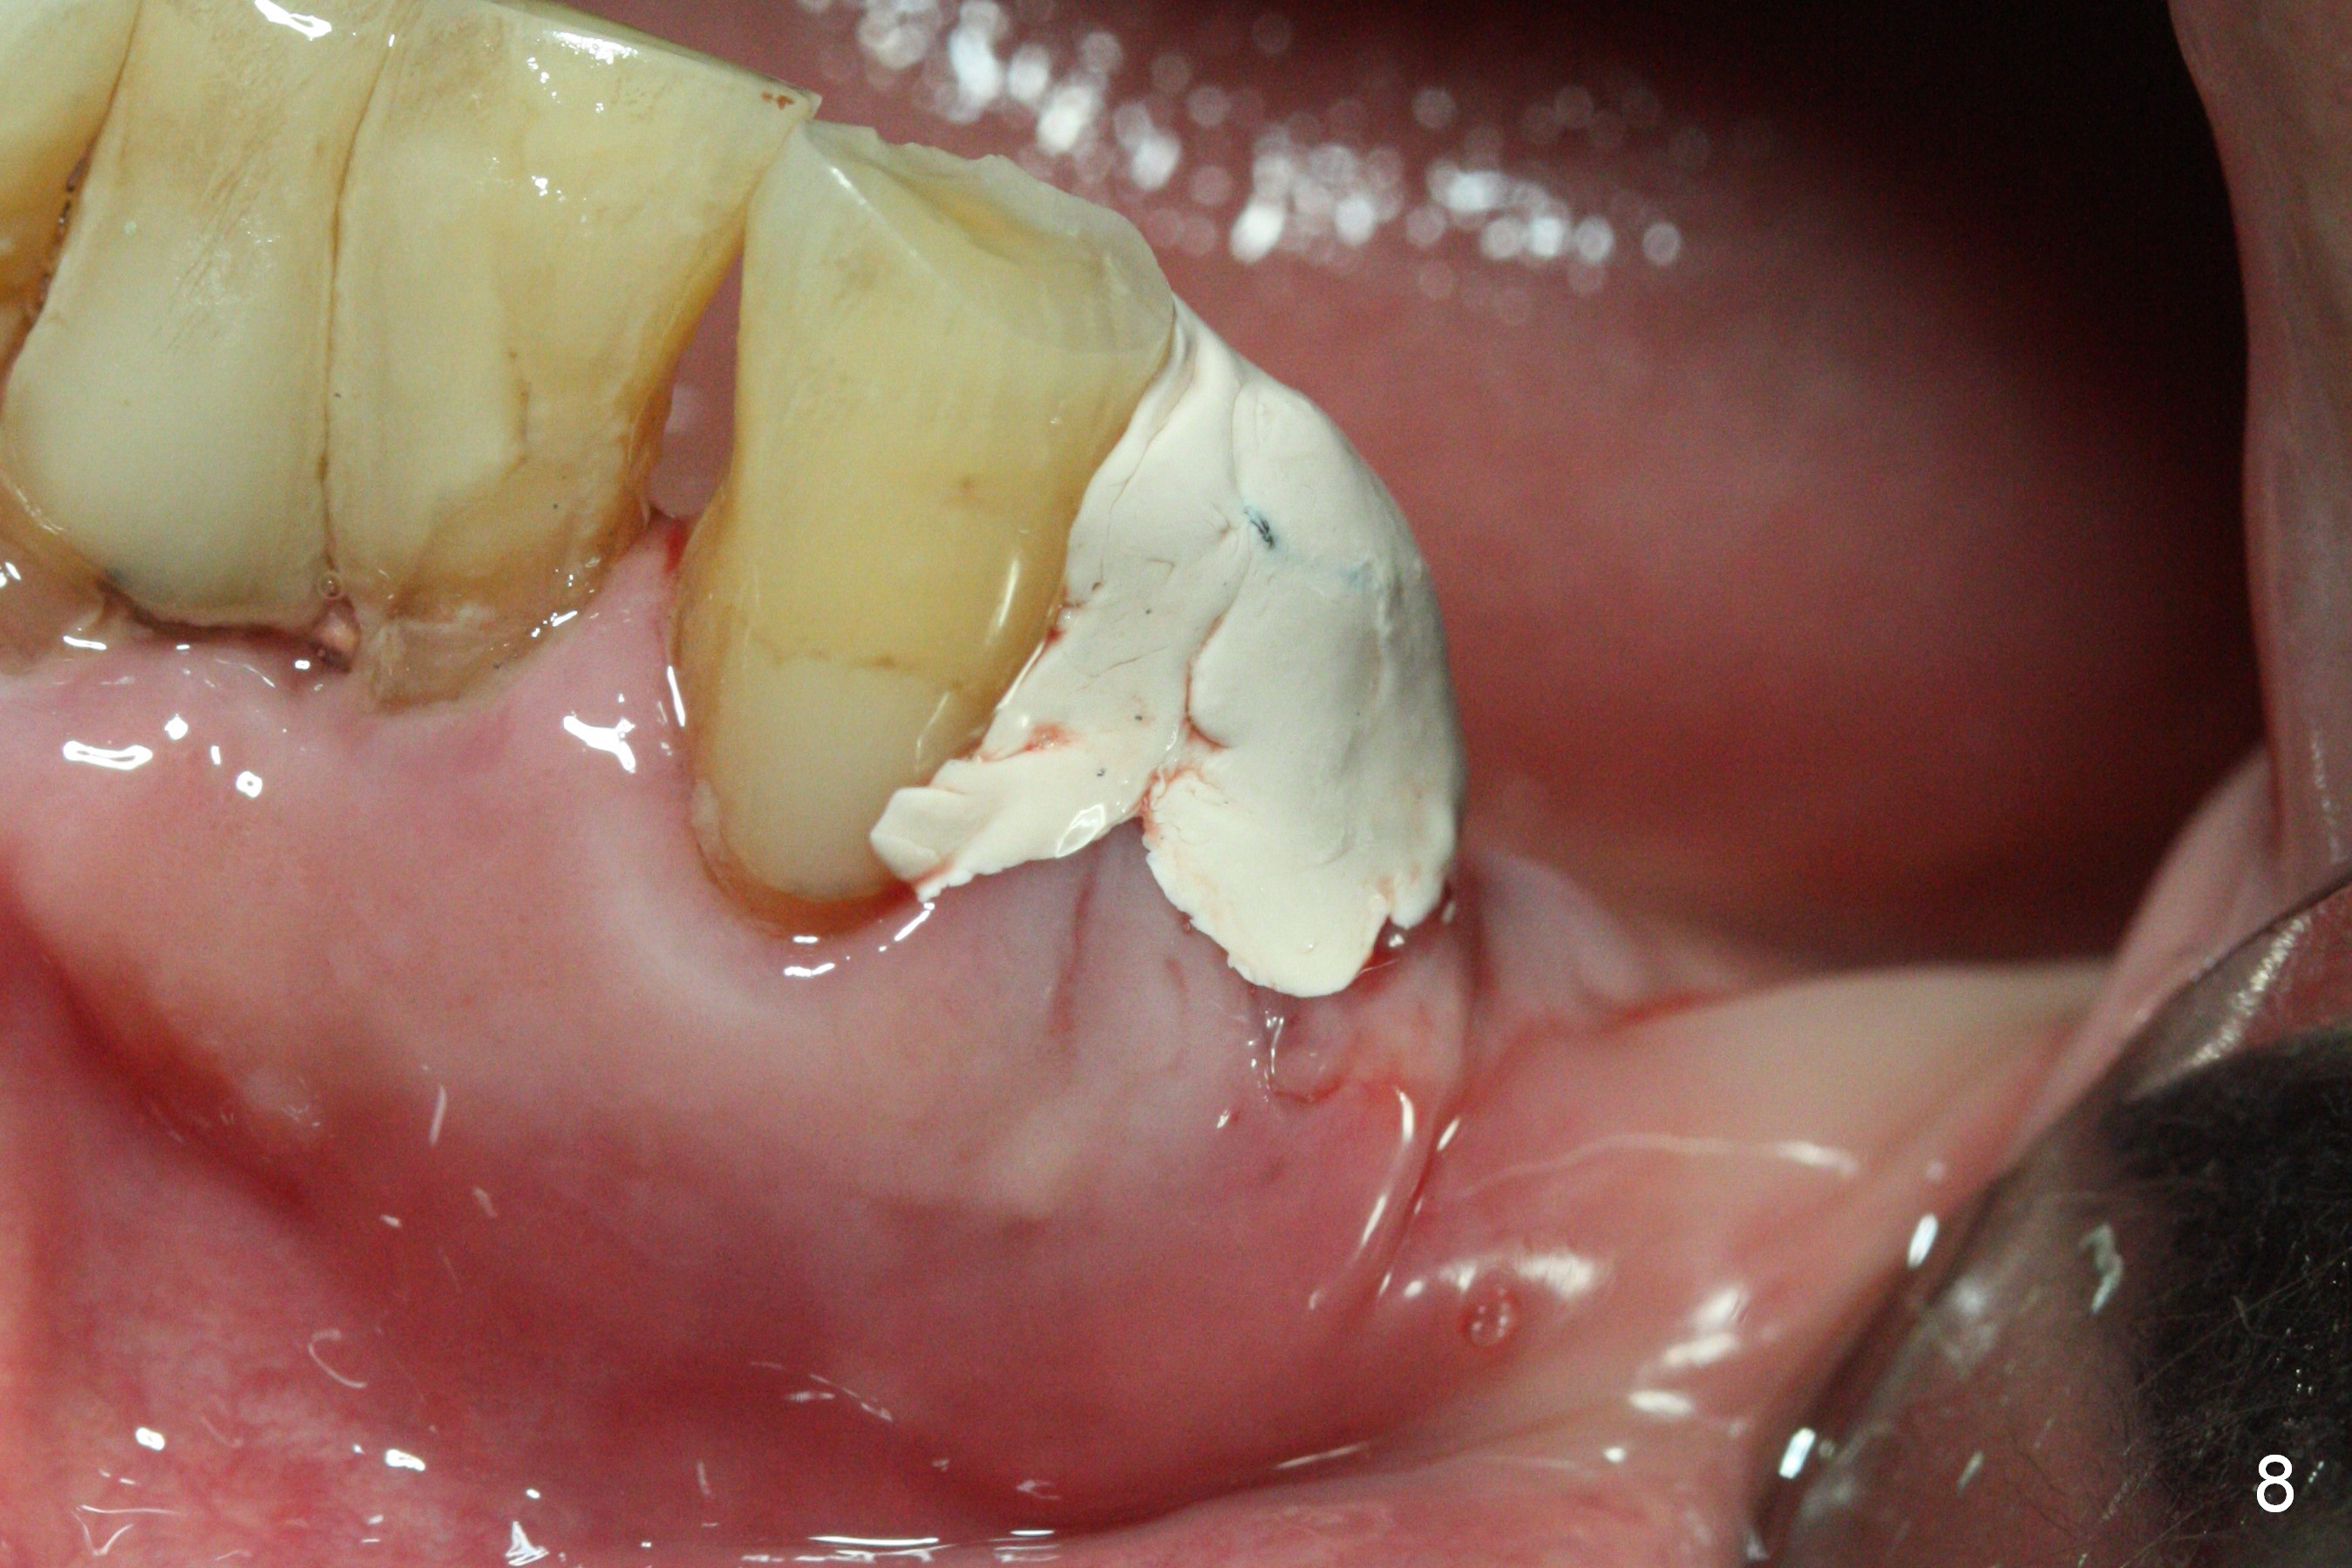

A 72-year-old man presents to clinic for implants because of pain associated with wearing the lower partial. The teeth #21, 24, 25 and 31 seem to be non-salvageable and are going to be replaced by implants so that the lower RPD can be reused (Fig.1). The edentulous ridge is atrophic (Fig.9 *). The upper complete denture appears to be functional. Since the tooth #21 is symptomatic (Fig.2) and the patient has chronic TMJ dislocation, the affected tooth is extracted first (Without antibiotic socket treatment) for immediate implant (Fig.3 (1.5 mm drill (placed more lingually)). The lower RPD is used as a surgical guide (Fig.4 (3 mm drill in place)). When a 3.8x16 mm implant is placed with bone graft (Fig.5 *), the underlying neurovascular bundle is undetected. A small field of panoramic X-ray is retaken; it seems that there is enough clearance from the Mental Foramen (Fig.2,6,7 (red dashed line)) and the Incisive Canal (pink dashed line). The implant is then placed 2 mm more apically (Fig.7) to reduce the chance of periimplantitis since the buccal plate is lost. A 5.5x5(5) mm abutment is placed (Fig.5) with more graft. The access of the abutment is left open so that a part of periodontal dressing is inserted for additional retention (Fig.8,9). The RPD is placed back for adaptation of the dressing. The patient is advised not to wear the RPD postop to reduce micromovement.